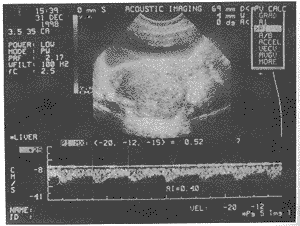

图3 子宫骶韧带平滑肌瘤

阔、骶韧带平滑肌瘤组瘤体内血流非常丰富呈网状和条状,子 宫浆膜下肌瘤组血流丰富呈条状和点状,子宫肌壁间肌瘤和阴道壁肌瘤血流较丰和不丰呈星 状或点状(图1~3)。瘤体内动脉血流参数值见表2。

2.良性盆腔平滑肌瘤亦可出现丰富的低阻力型动脉频谱。本组资料中,部分阔韧带肌瘤以 及少数子宫浆膜下肌瘤和个别子宫肌壁间肌瘤均可检出低阻力型动脉血流,RI≤0.40,且这些平滑肌 瘤瘤体均较大,径线7~22cm(见图1~3)。近年来,恶性卵巢肿瘤内部血流阻力低于良性卵 巢肿瘤的报道甚多,以PI<1.0,RI<0.40作为诊断恶性卵巢肿瘤的分界值已为较多学者 所采纳〔1、3〕,由于阔韧带平滑肌瘤部位特殊,应注意与恶性卵巢肿瘤相鉴别,前 者包块内部回声致密呈旋涡状或形成栅栏征,部分瘤体内可见不规则液性暗区〔2〕 ;后者回声不均,可见光斑光团或暗区,且多伴有腹水,可资鉴别〔1〕。而对于子 宫肌壁间和浆膜下肌瘤,只要重视黑白超声的图像特征,并认识到有出现低阻力型动脉频谱 的可能性,鉴别诊断应当不成问题。